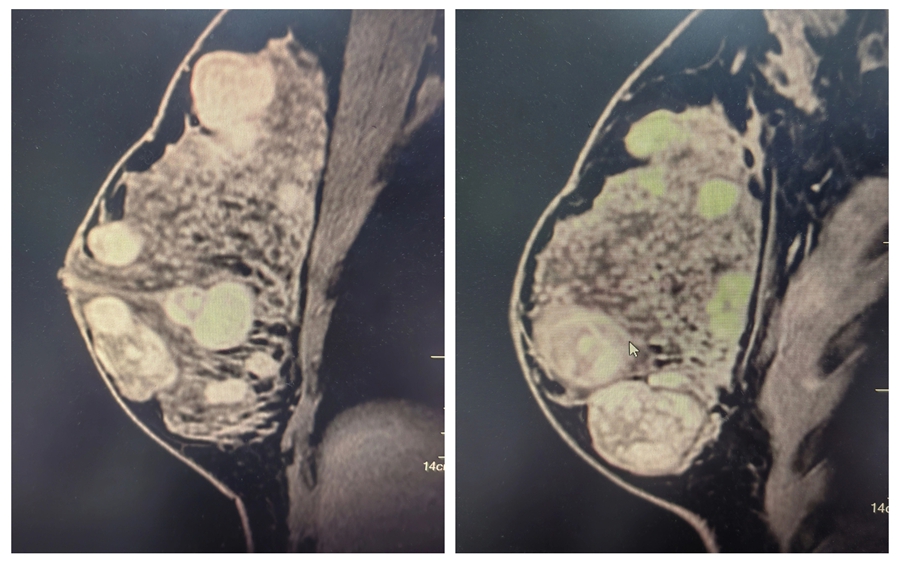

△乳腺核磁共振檢查可見(jiàn)多結(jié)節(jié)分布

患者曉莉(化名)因自覺(jué)雙側(cè)乳房“疙疙瘩瘩”前來(lái)就診,乳腺超聲檢查令人心頭一緊,雙側(cè)乳房都長(zhǎng)了結(jié)節(jié),右側(cè)乳腺更多,部分小結(jié)節(jié)融合成大結(jié)節(jié),最大的直徑達(dá) 5 厘米。